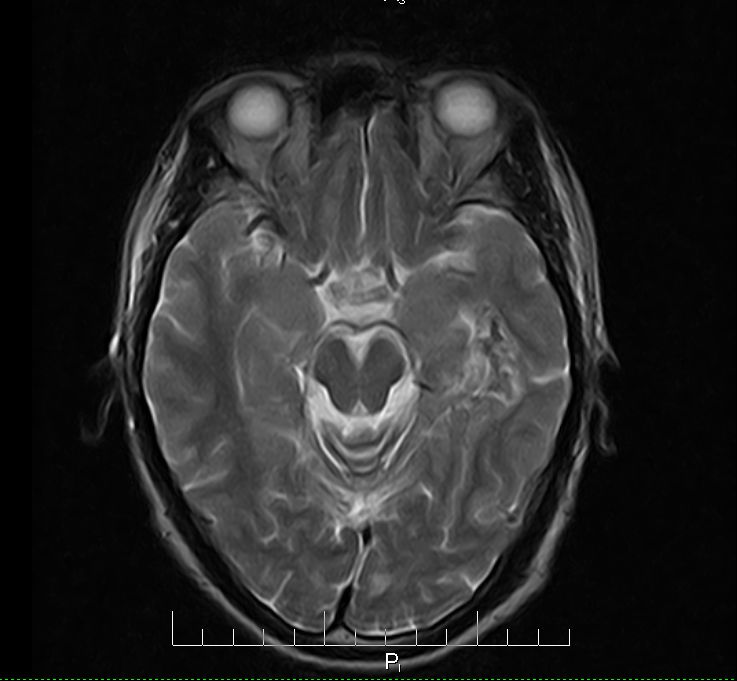

标题: MRI2379:30岁,男,癫痫10年,请各位看一下;CT示:左颞叶钙 [打印本页]

标题: MRI2379:30岁,男,癫痫10年,请各位看一下;CT示:左颞叶钙

左颞叶区见不规则点状混杂信号影

支持2楼 左颞叶区见不规则点状混杂信号影,考虑动静脉畸形。

考虑左侧颞叶脑血管畸形(avm)。----t1低等高混杂信号,t2等高信号周边较多流空血管影[冠状位明显],mra左侧大脑中动脉受压,远侧聚集.

考虑avm,建议行增强扫描,看供血a与引流v,以明确诊断。